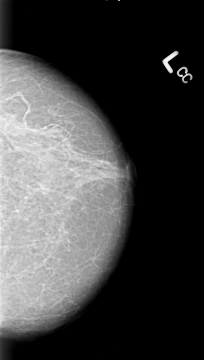

B_3013_1.LEFT_CC

LEFT_CC LINES 4312 PIXELS_PER_LINE 2440 BITS_PER_PIXEL 12 RESOLUTION 50 NON_OVERLAY

LESION_TYPE MASS SHAPE IRREGULAR-ARCHITECTURAL_DISTORTION MARGINS SPICULATED

ASSESSMENT 5

SUBTLETY 5

PATHOLOGY MALIGNANT